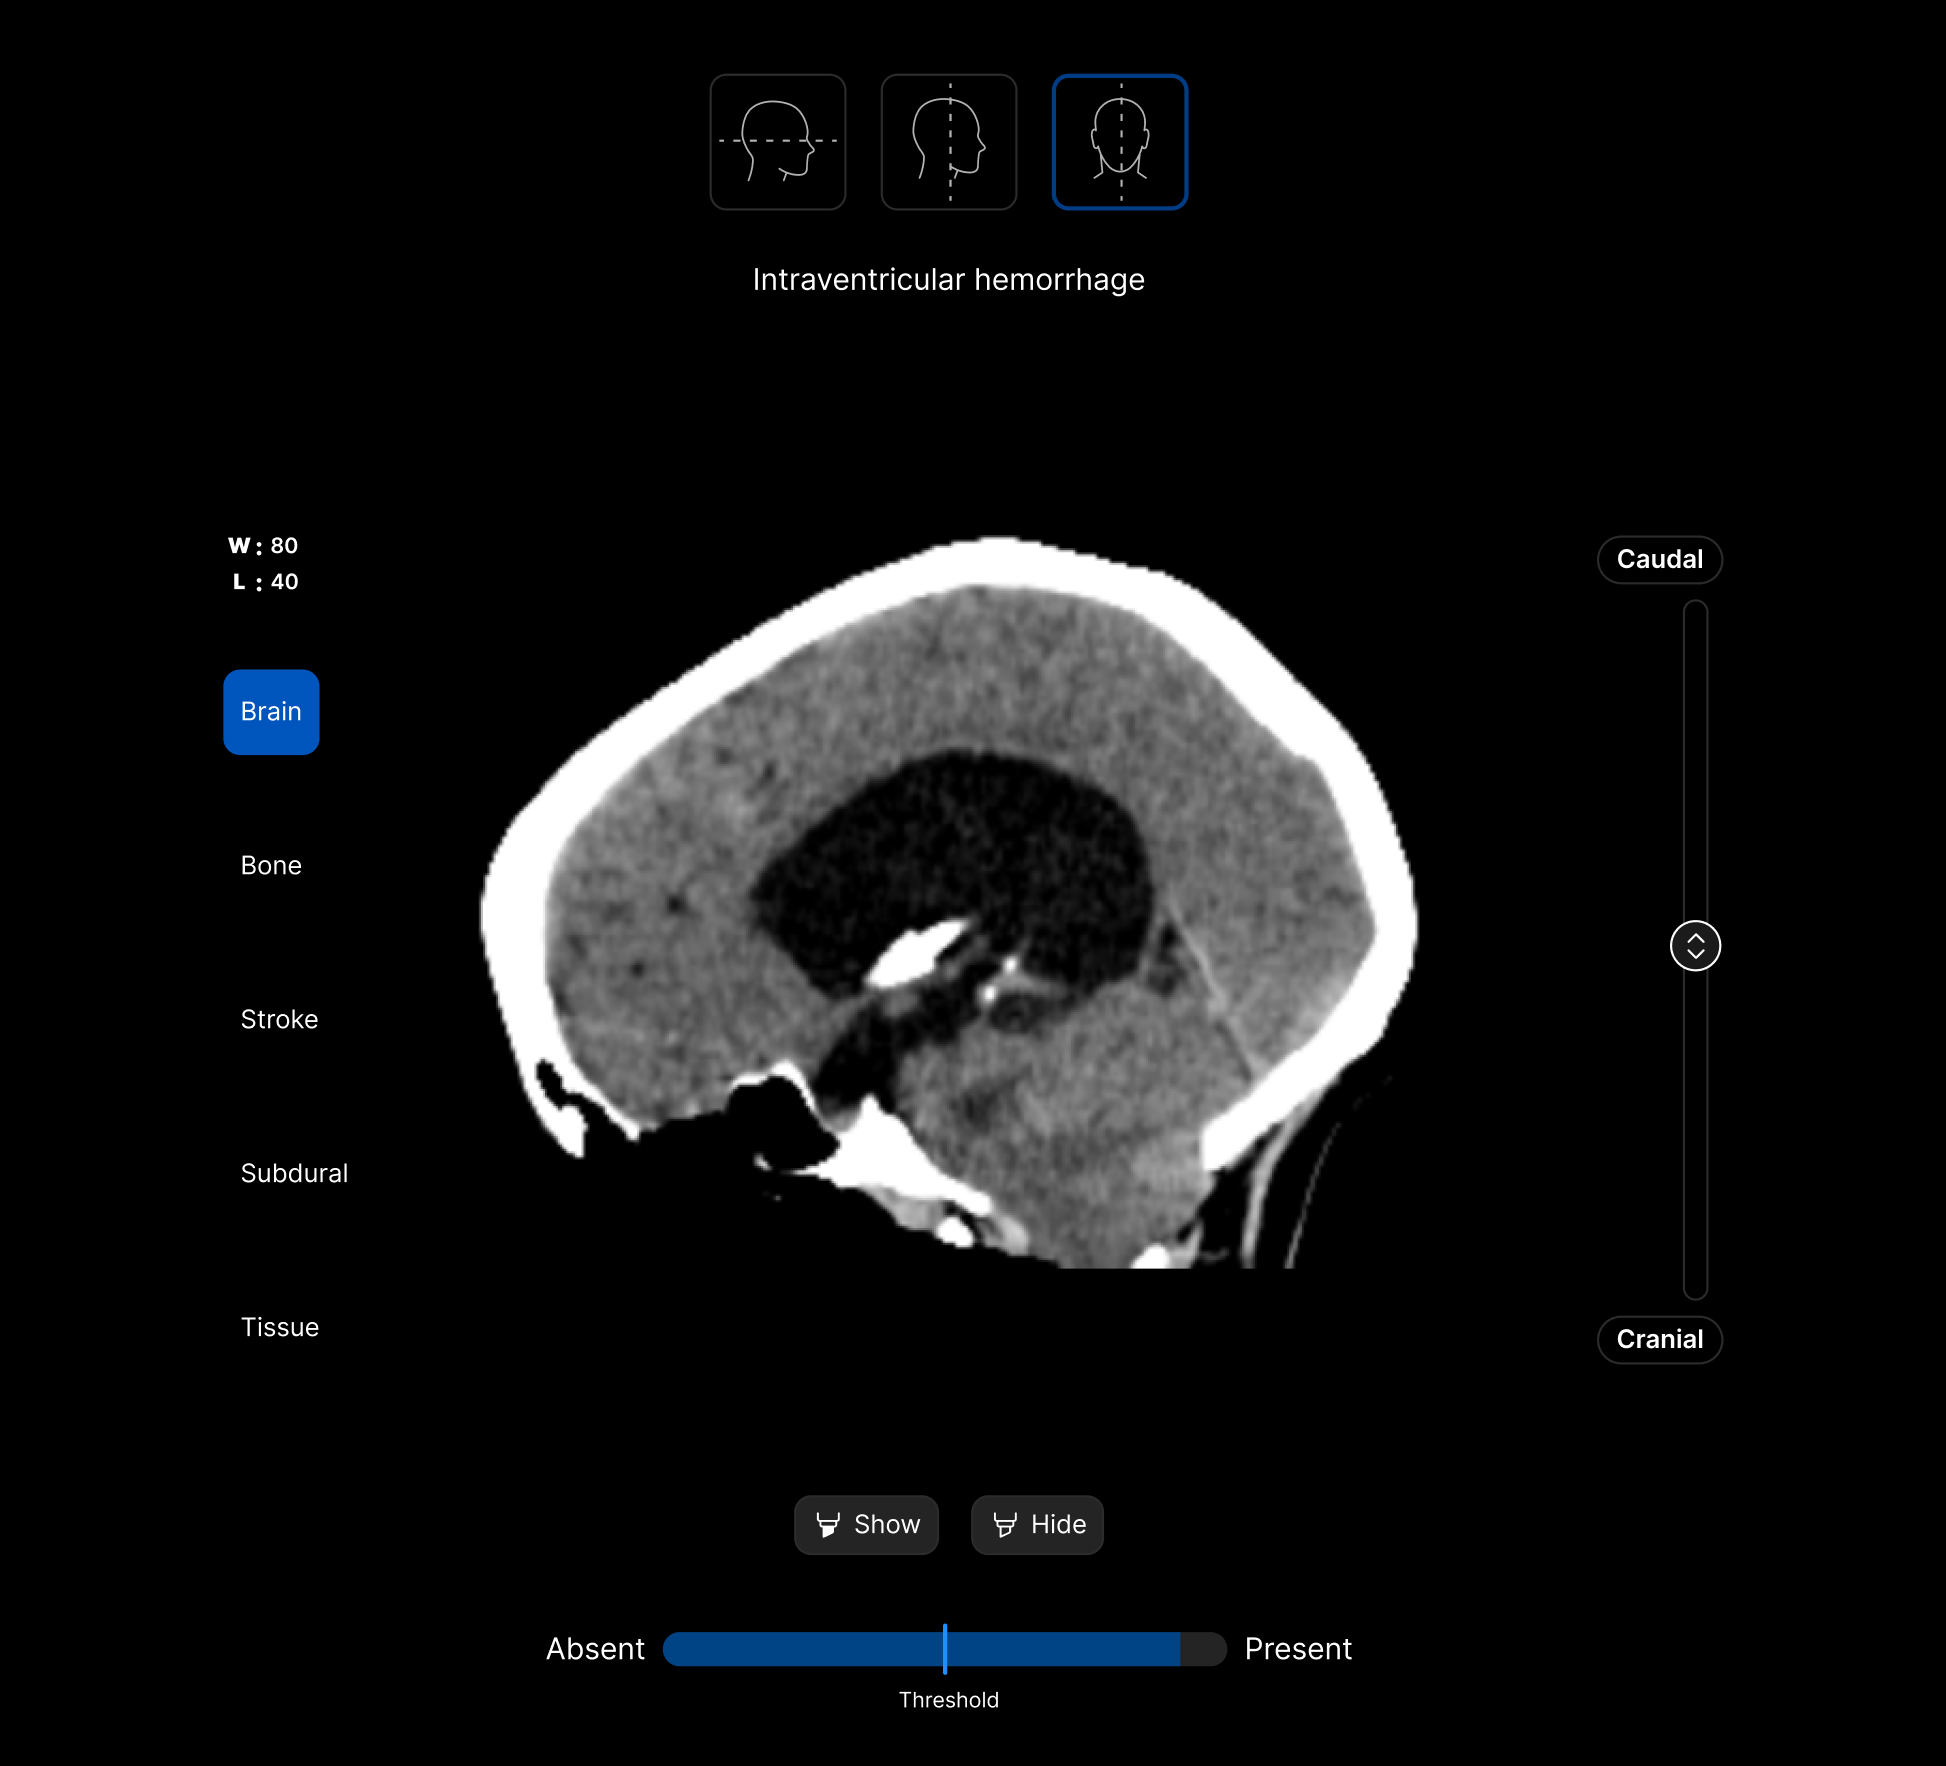

The UI integrates seamlessly with PACS/ RIS, displaying a resizable, no-click overlay window with findings and localisation.

Customisable features.

Customisable thresholds, for individual findings (to optimise for sensitivity / specificity) to tailor the workflow to your clinical setting or population.